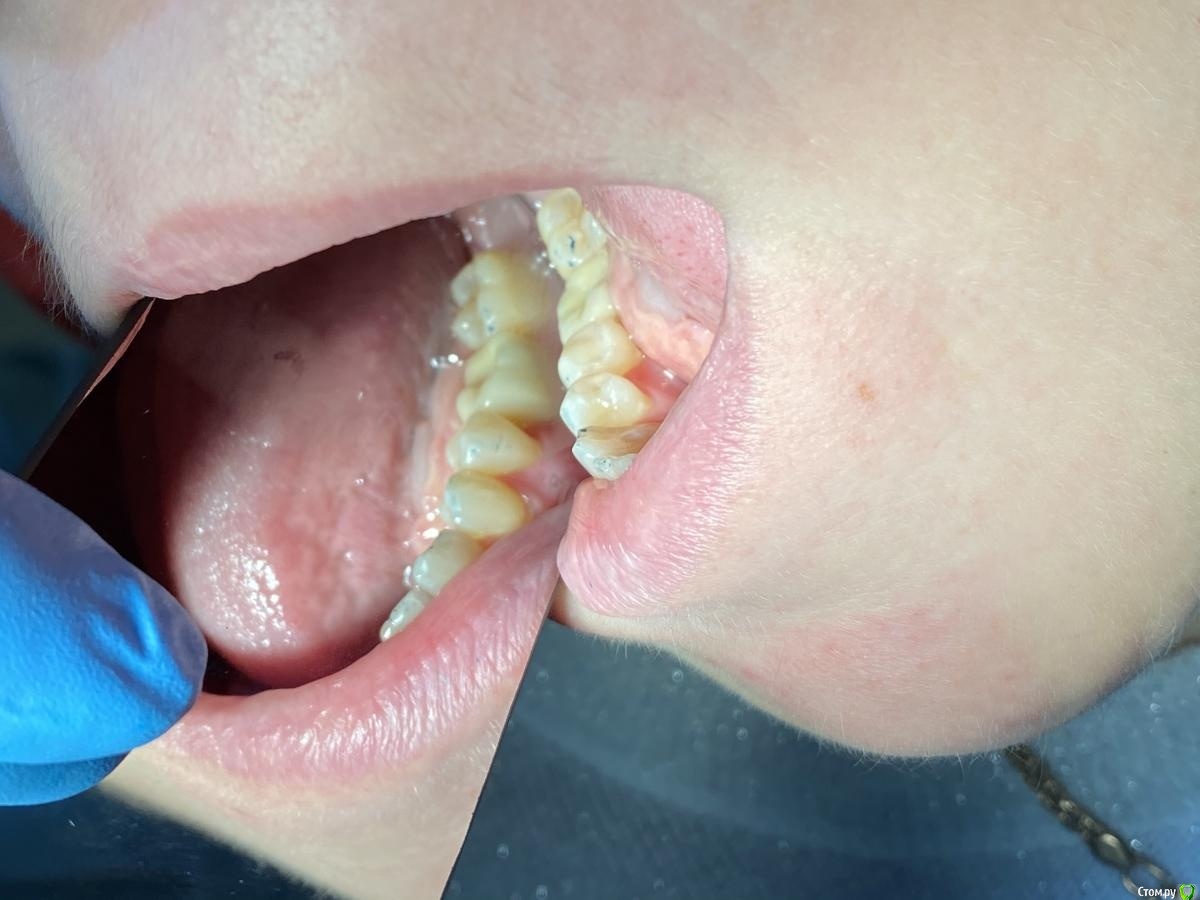

Женька Опубликовано 6 августа, 2020 Автор Поделиться Опубликовано 6 августа, 2020 (изменено) Язычный гребень выше вестибулярногоВроде тут хорошо видно, что как раз наоборот. Вестибулярный край десны выше, а язычно "яма".@Irouil, возвращаясь к 39 сообщению, немного не понял куда резать Может есть возможность схему какую-то показать или пример разрезов или вообще видеозапись. Изменено 6 августа, 2020 пользователем Женька Ссылка на комментарий

Женька Опубликовано 14 сентября, 2020 Автор Поделиться Опубликовано 14 сентября, 2020 Ну как-то вот так... Ссылка на комментарий

Irouil Опубликовано 14 сентября, 2020 Поделиться Опубликовано 14 сентября, 2020 (изменено) Не идеально, конечно, но я бы отправил уже на протезирование так на Вашем месте, прикрепленка есть, кортикалка по шейку Если включать перфекциониста, то можно пончо сделать, но нужно отслоиться через прикрепление эпителиальное, нужно и увеличение, и тунельный острый инструмент или микро хирургическое лезвие, и навык. Испортить тут можно гораздо больше, чем улучшить Основание абатмента пониже и пошире просто взять и пациента натаскать на гигиену, все ок будет Изменено 14 сентября, 2020 пользователем Irouil 1 Ссылка на комментарий

Женька Опубликовано 14 сентября, 2020 Автор Поделиться Опубликовано 14 сентября, 2020 Не идеально, конечно, но я бы отправил уже на протезирование так на Вашем месте, прикрепленка есть, кортикалка по шейку Если включать перфекциониста, то можно пончо сделать, но нужно отслоиться через прикрепление эпителиальное, нужно и увеличение, и тунельный острый инструмент или микро хирургическое лезвие, и навык. Испортить тут можно гораздо больше, чем улучшить Основание абатмента пониже и пошире просто взять и пациента натаскать на гигиену, все ок будетЯ придерживаюсь этого же мнения...Я скорее испорчу то, что получилось. Эти фото с формирователем 4.5, 3 месяца ходили с 4.0На этапе прикручивания 4.5, пациентка отметила легкое жжение... на фдм метрогил был...вот думаю, то ли это на метрогил такая реакция, то ли я что-то задавил? Планировали на тибейзе geo делать... там варианта пошире насколько я знаю нет. 4.5 и размеры по вертикали cut и длинные З.Ы. Вчера у Ильгама Ирековича на курсе впервые познакомился с галилеями от экзама... всего 2.8, быстро привыкли глаза (учитывая, что они не индивидуально под меня были)... это просто какой-то другой мир. Ссылка на комментарий